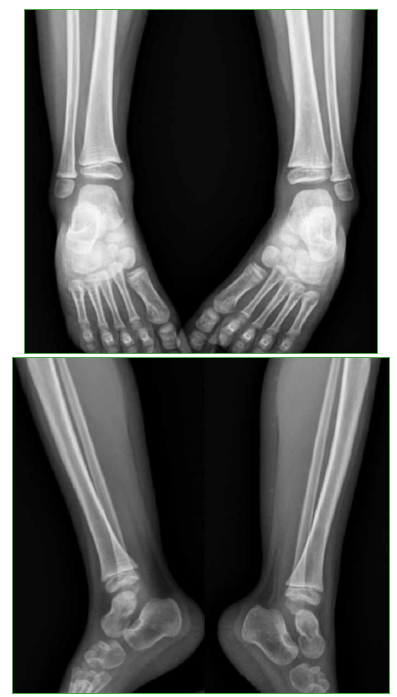

Osteomielitis de tibia secundaria a la vacuna BCG en un paciente pediátrico inmunocompetente. Reporte de un caso

Conclusiones: El compromiso óseo secundario a la vacuna BCG en pacientes previamente sanos es muy raro. Es importante sospecharlo, para diagnosticarlo y administrar el tratamiento adecuado. Se obtuvieron buenos resultados administrando fármacos antituberculosos, sin necesidad de limpieza quirúrgica.